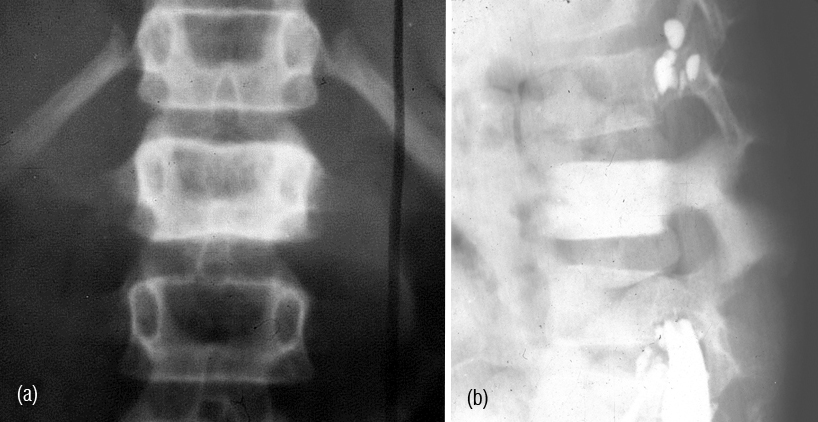

It radiologically shows a spectrum of manifestations. The bones particularly, in axial skeleton may present with multiple compression fractures. In 10-15% of cases, classical punched out lesions of the skull may be noted. In long tubular bones, pathological fractures are common with associated soft tissue swelling. In early skeletal lesions, moth eaten type of appearance is observed without any periosteal reaction (Figure 6ab). MRI is more sensitive to depict bone marrow lesions, whereas radionuclide scintigraphy with technetium 99 compounds is not that sensitive (Figure 7abcdef). The radiological appearances are listed in Table 3.

Figure 6: Multiple Myeloma – (a) Diffuse osteopenia with loss of trabeculae, (b) lytic lesions in the bodies.

Figure 7: (a,b,c) Multiple myeloma with osteopenia and early collapse of vertebral bodies BC MRI of the same patient. (d) plain films, (e, f) MRI.